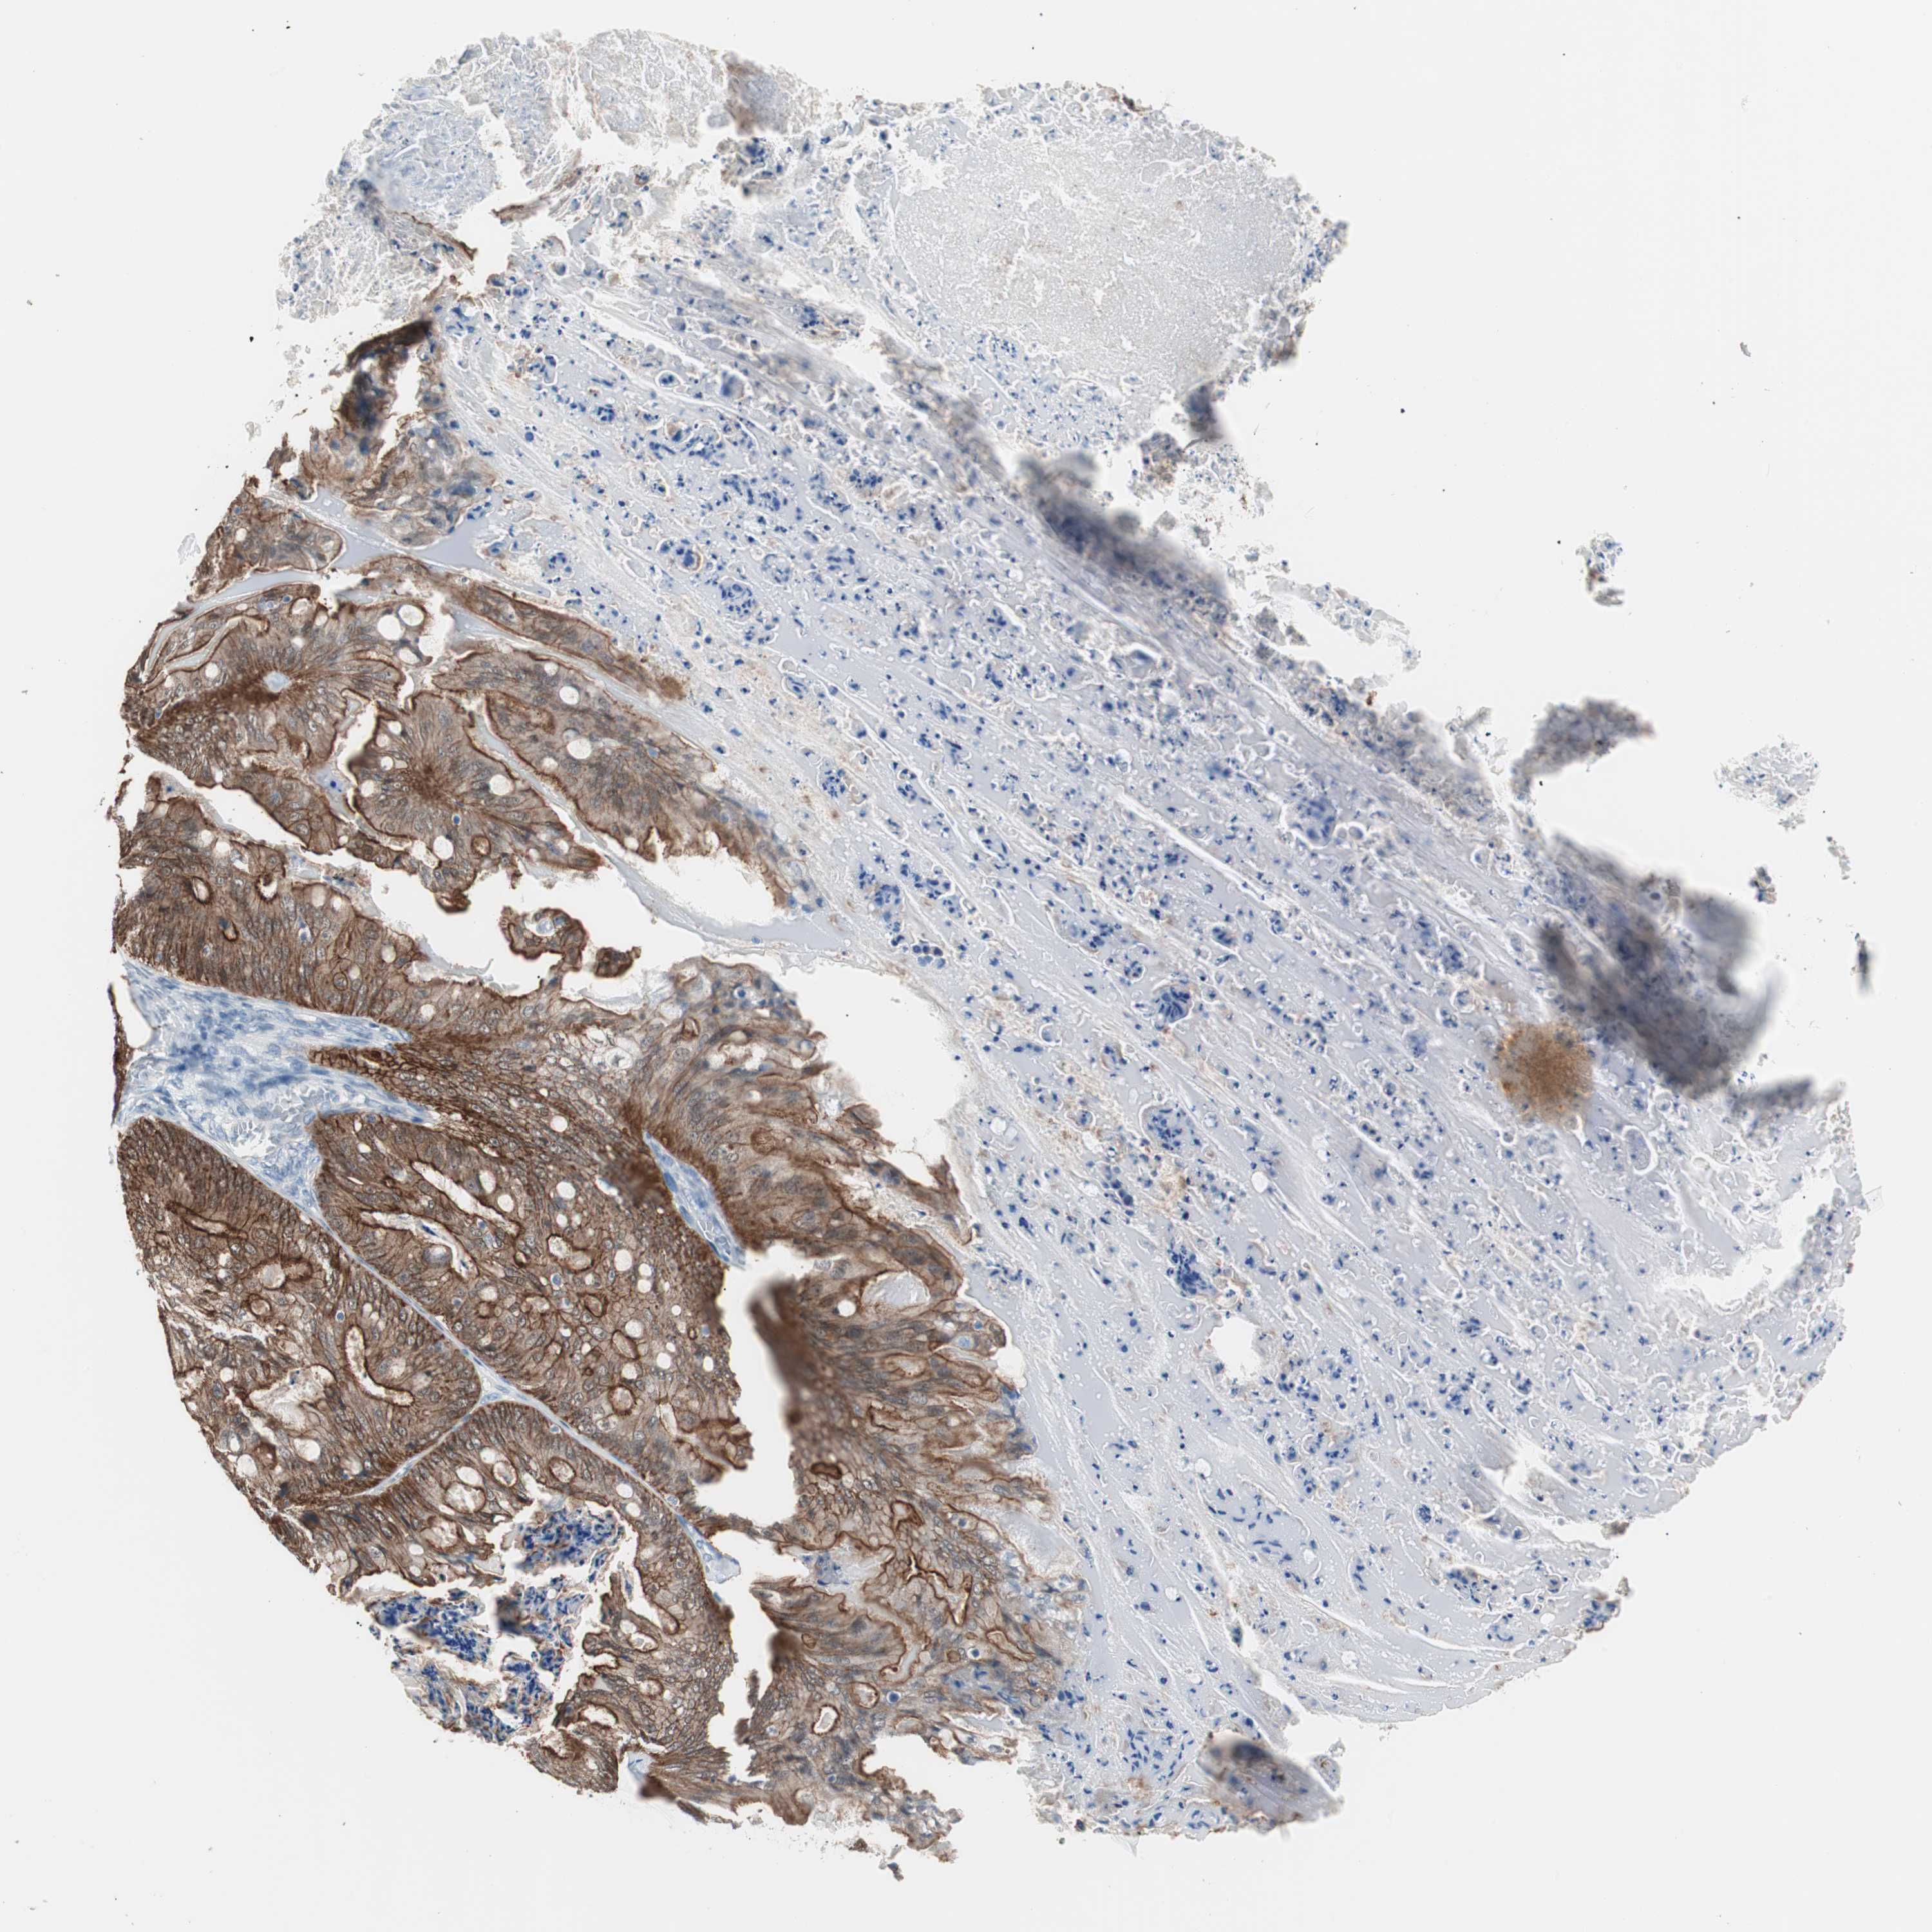

OVARIAN CANCER - Protein expressioni

A mouse-over function shows sample information and annotation data. Click on an image to view it in a full screen mode. Samples can be filtered based on level of antibody staining by selecting one or several of the following categories: high, medium, low and not detected. The assay and annotation is described here.

Note that samples used for immunohistochemistry by the Human Protein Atlas do not correspond to samples in the TCGA dataset.

Antibody stainingi

Antibody staining in the annotated cell types in the current human tissue is reported as not detected, low, medium, or high, based on conventional immunohistochemistry profiling in selected tissues. This score is based on the combination of the staining intensity and fraction of stained cells.

Each image is clickable and will lead to virtual microscopy that enables deeper exploration of all samples and also displays staining intensity scores, fraction scores and subcellular localization as well as patient and tissue information for each sample.

Antibody HPA006884

Antibody HPA006885

Antibody CAB002452

Staining

High

Medium

Low

Not detected

Intensity

Strong

Moderate

Weak

Negative

Quantity

>75%

75%-25%

<25%

None

Location

Nuclear

Cytoplasmic/membranous

Cytoplasmic/membranous,nuclear

Cystadenocarcinoma, serous, NOS

Carcinoma, endometroid

Carcinoma, NOS

Cystadenocarcinoma, mucinous, NOS